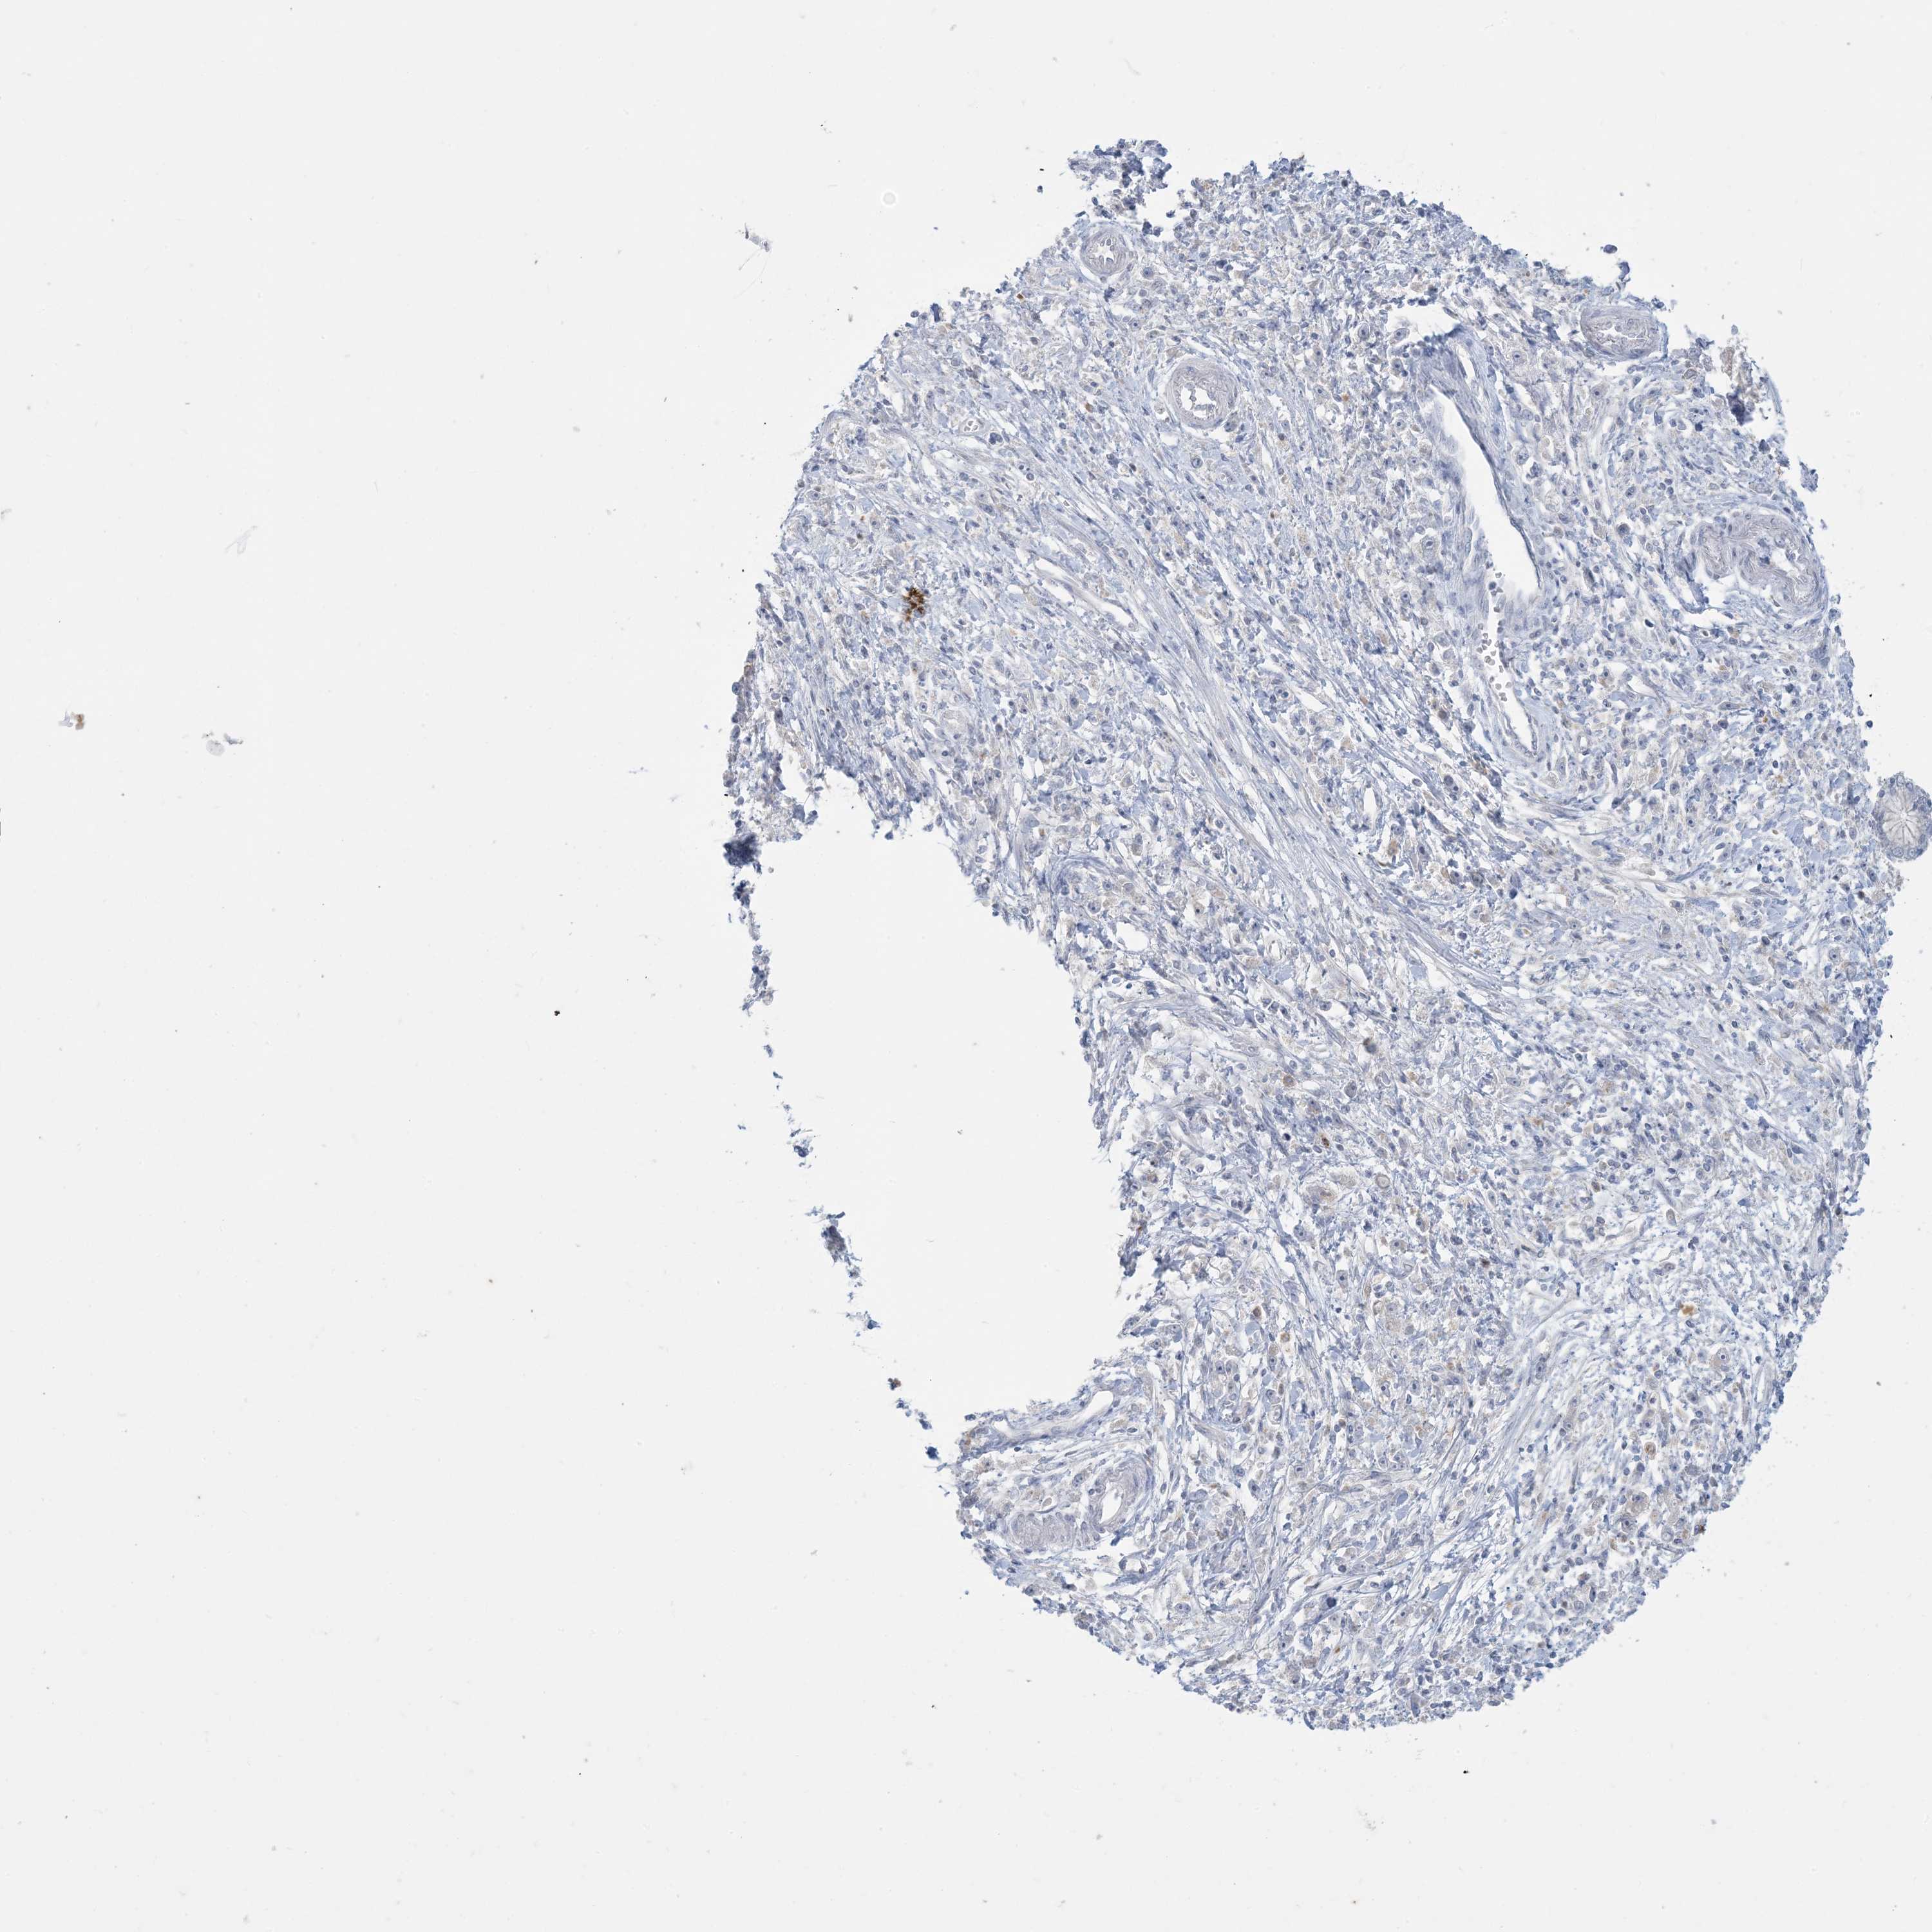

STOMACH CANCER - Protein expressioni

A mouse-over function shows sample information and annotation data. Click on an image to view it in a full screen mode. Samples can be filtered based on level of antibody staining by selecting one or several of the following categories: high, medium, low and not detected. The assay and annotation is described here.

Note that samples used for immunohistochemistry by the Human Protein Atlas do not correspond to samples in the TCGA dataset.

Antibody stainingi

Antibody staining in the annotated cell types in the current human tissue is reported as not detected, low, medium, or high, based on conventional immunohistochemistry profiling in selected tissues. This score is based on the combination of the staining intensity and fraction of stained cells.

Each image is clickable and will lead to virtual microscopy that enables deeper exploration of all samples and also displays staining intensity scores, fraction scores and subcellular localization as well as patient and tissue information for each sample.

Antibody CAB037085

Staining

High

Medium

Low

Not detected

Intensity

Strong

Moderate

Weak

Negative

Quantity

>75%

75%-25%

<25%

None

Location

Nuclear

Cytoplasmic/membranous

Cytoplasmic/membranous,nuclear

Adenocarcinoma, NOS